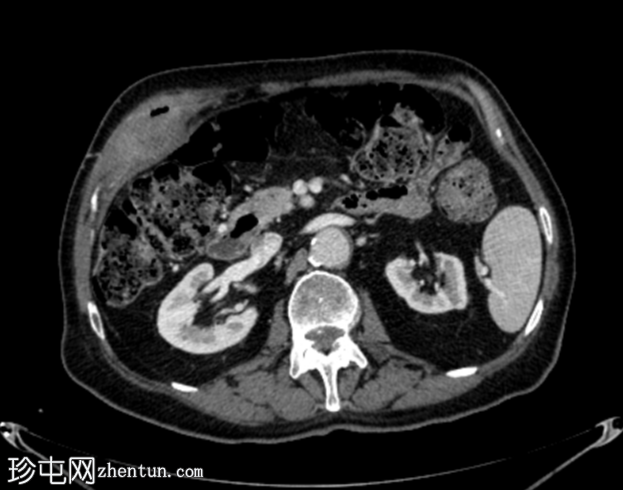

轴位增强扫描

动脉期

胆囊底部可见一枚较大的(3厘米)高密度结石,胆囊壁增厚并强化,主要位于胆囊底部。胆囊壁可见一小穿孔,感染扩散至胆囊外,并在肝下区可见气体腔。感染进一步扩散至腹壁肌肉,腹壁肌肉内可见脓肿,边缘强化明显,囊性坏死中心,腔内可见气体腔。十二指肠第一段与炎症胆囊粘连。

检查结果提示急性胆囊炎合并腹壁脓肿。

右侧膀胱有两个小憩室。